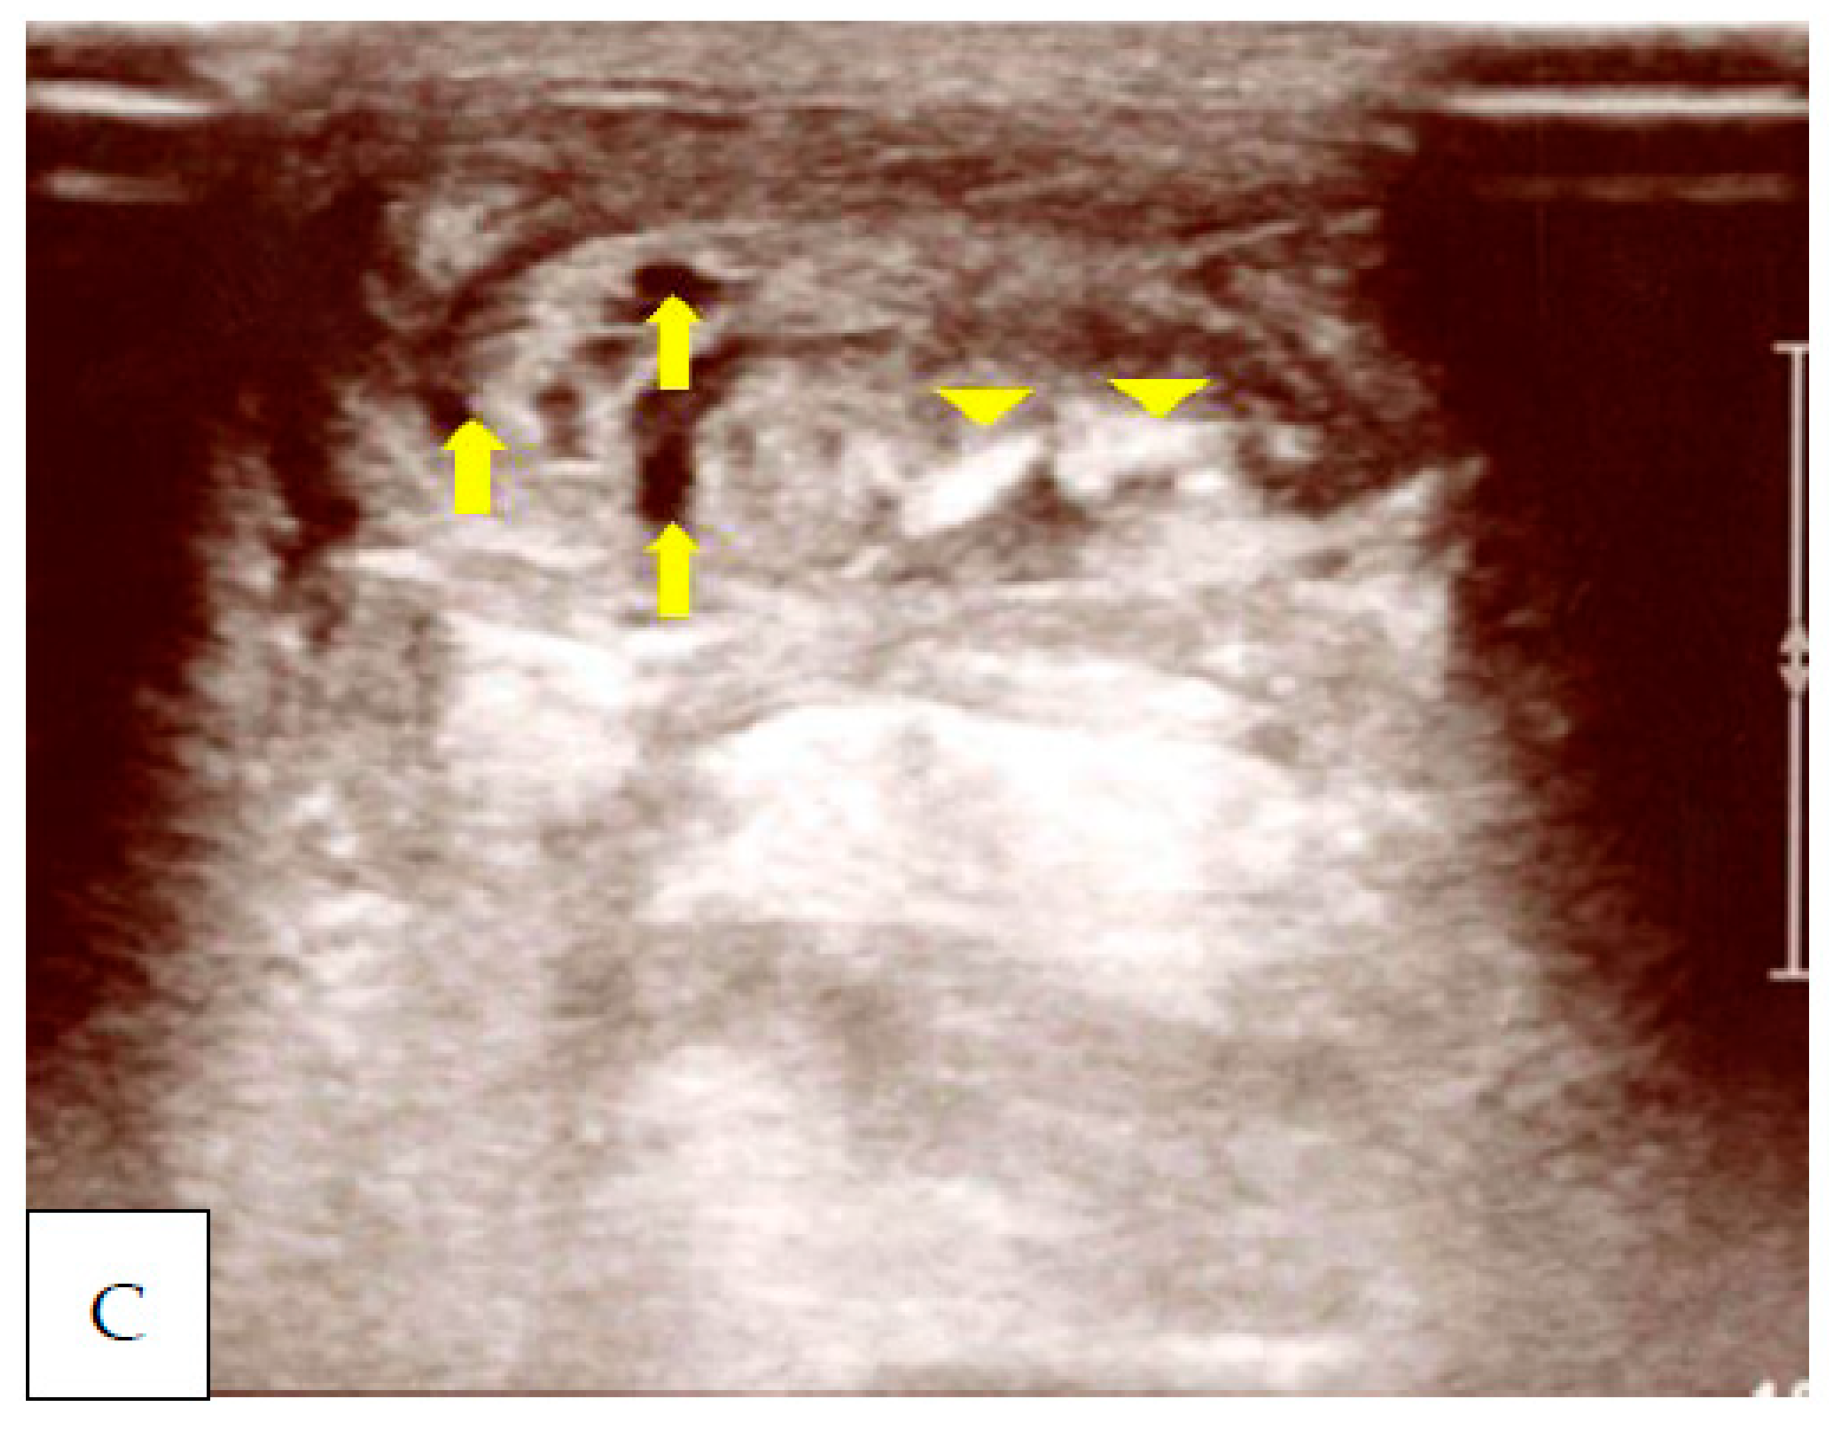

2. Case Presentation